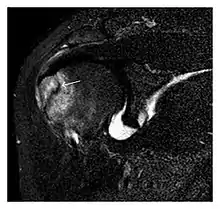

The greater tuberosity of the humerus is also an illustrative location of occult fractures. The osseous injury may follow seizures, glenohumeral dislocation, forced abduction, or direct impaction. They are commonly discovered on MRI in symptomatic patients with suspicion of rotator cuff tear. Coronal images are best suited for detection. They appear as crescentic oblique lines surrounded by a bone marrow edema pattern (Figure 5). The rotator cuff must be inspected since associated ligamentous lesions are common. In the ankle, malleoli and tarsal bones should be checked carefully for any cortical disruptions and radiolucent lines that may reveal a fracture. Awareness of the exact location of the pain will help direct the attention of the interpreter when searching for very subtle signs of fracture (Figure 6).[1]

a

b

Figure 7: Fatigue fracture of the talus in a 25-year-old male basketball player with right hind foot and ankle pain, without history of trauma, and a normal initial radiograph (not shown). (a) One-month followup lateral radiograph shows normal appearance. (b) Sagittal T1-weighted MRI shows an irregular fracture line (arrow) within an ill-defined area of hypointensity corresponding to bone marrow edema.[1]